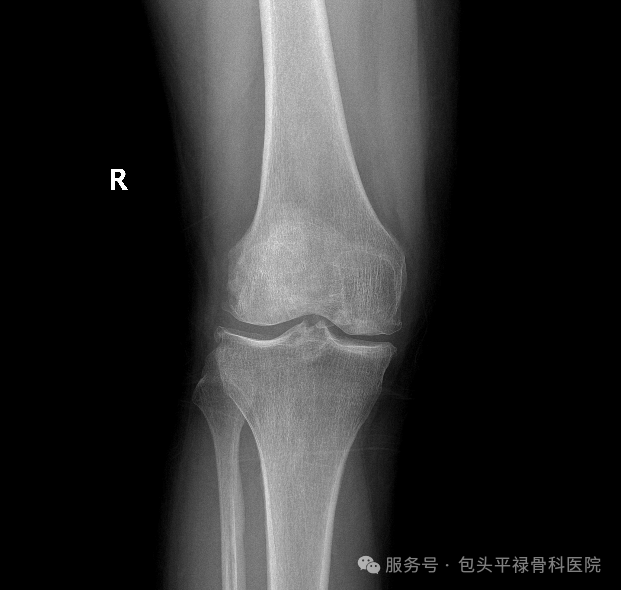

右膝关节游离体,图源:包头平禄骨科医院